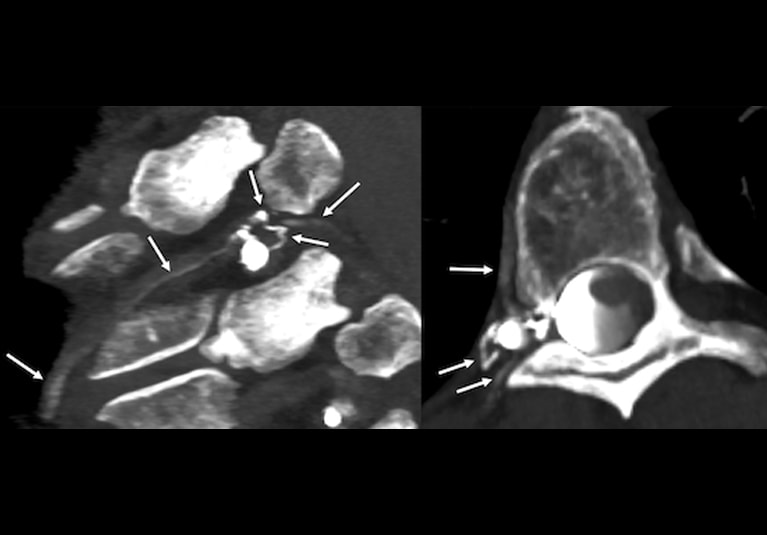

Photon-counting detector CT images identify a cerebral spinal fluid (CSF)-venous fistula in a patient who experienced years of intractable headaches. The patient's brain and spinal MRI had findings suggestive of spontaneous intracranial hypotension. The CT images — obtained almost immediately after iodinated contrast injection into the thecal sac — clearly show contrast dye leaking into multiple veins (arrows). The fistula was successfully treated with transvenous liquid embolization, and the patient's symptoms resolved overnight.

CSF-venous fistulas are notoriously difficult to localize. The contrast dye used in imaging leaks into a vein and is quickly carried away with CSF into the central venous system. "It's a very transient image finding," Dr. Madhavan says.